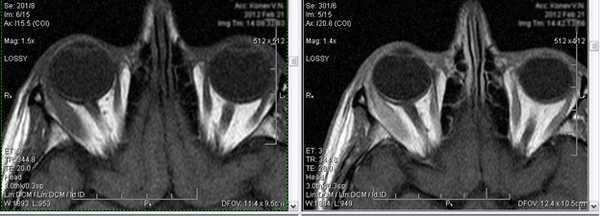

3. Миозит.

Возникновение данного заболевания, зачастую, связано с простудным фактором. Проявляется острой болью в глазах и глазницах, особенно при тех движениях глазного яблока, в которых участвуют пораженные мышцы. Далее развивается экзофтальм, диплопия.

Для более детального изучения выявляемой патологии возможно проведение внутривенного контрастирования (введения контрастного вещества):

На изображении слева-снимок без контрастного препарата, на изображении справа - с контрастированием.